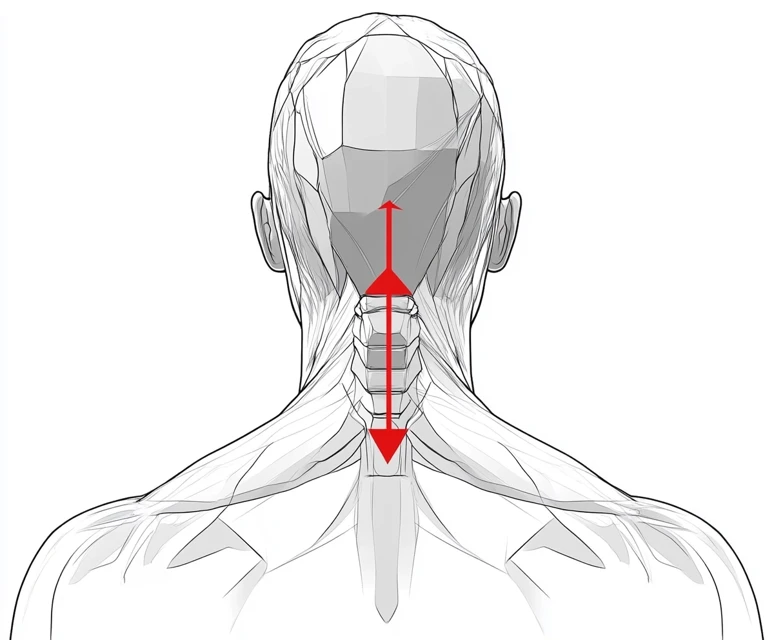

물리치료는 목디스크 환자에게 가장 일반적으로 권장되는 치료법입니다. 물리치료는 통증 완화와 회복을 돕는 다양한 기술을 포함합니다. 물리치료사는 환자의 상태에 맞춘 운동 프로그램을 설계하여 근육을 강화하고 유연성을 향상시킵니다. 주요 치료 방법으로는:

- 견인 요법: 목의 압력을 줄이고, 디스크의 위치를 개선하기 위해 견인 장비를 사용합니다.

- 슴렛 운동 및 스트레칭: 목과 어깨 부위의 근육을 강화하고 이완하는 데 도움을 주는 운동을 포함합니다.